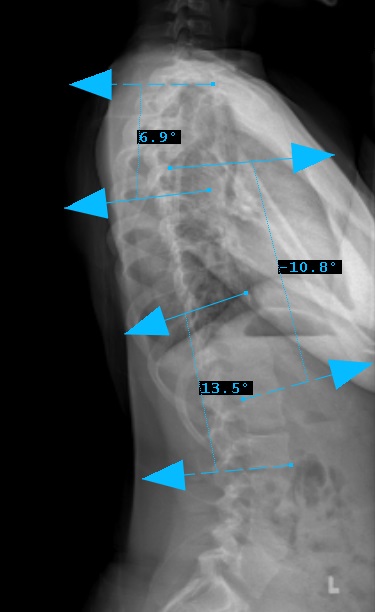

Preop: 1C- Examples

Preop LAT View

Curve Type 1

Thoracic curve major, other curves non-structural (bend out to <25o)

Lumbar modifier C

CSVL does not touch apex of lumbar curve

(apex - L1/2 disc)

STEP 3

Sagittal Modifier ( - )

T5-T12 in the <10o range

Therefore, Classification is Type 1C-